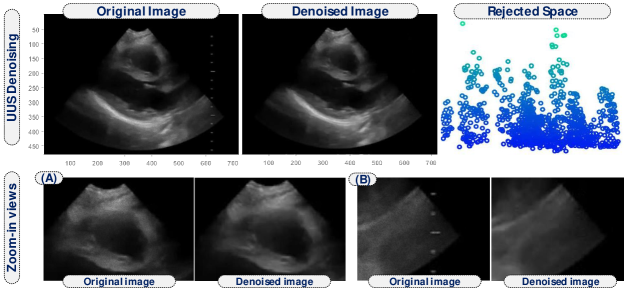

As we stated before, another main motivation to promote low-rank representation instead of using the full Casorati matrix is to reduce noise. This is accomplished by eliminating the subspace where the noise relies, which results in retrieving a subspace with only relevant information. Noise, which normally relies on another subspace due to its characteristics, is rejected from the solution (see Figure 3). This eliminates artifacts in the subsequent deformation computation.

In the last step, we use the invertibility in equation (1) to invert the low-rank representation back to the denoised video sequence . We will work with that sequence in the following section to extract the mechanical deformation field of the heart.